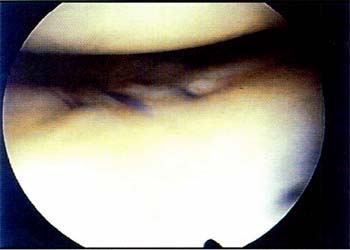

Complicaciones: 1) ruptura del ligamento biológico y sintético: 1 caso ; 2) limitación de la extensión: en 6 pacientes, limitaciones mayores de -10 grados; 3) limitación en la flexión: 18 casos con limitación entre 16 y 25 grados y 10 casos con limitaciones mayor a 25 grados; 4) dolor anterior en la rodilla: 24 casos (48%); 5) Parestesia temporaria: 2 casos (4%); 6) sinovitis persistente: 10 casos (20%); 7) rupturas del ligamento de poliéster: 10 casos (20%) (fig.3); 8) atrofia muscular: 6 casos (12%).

Segundas artroscopías: Se realizó en diez pacientes (20%) los cuales presentaban ruptura del ligamento de poliéster con el ligamento biológico intacto. Todos los casos examinados artroscópicamente presentaban sinovitis con vellosidades recubriendo los fragmentos del ligamento artificial. (Fig.4)

03_01_03_Fig3

Fig. 3 - Ruptura del ligamento de poliester.

03_01_03_Fig4

Fig. 4 - Vellosidadsinovial sobre un fragmento de Palies ter